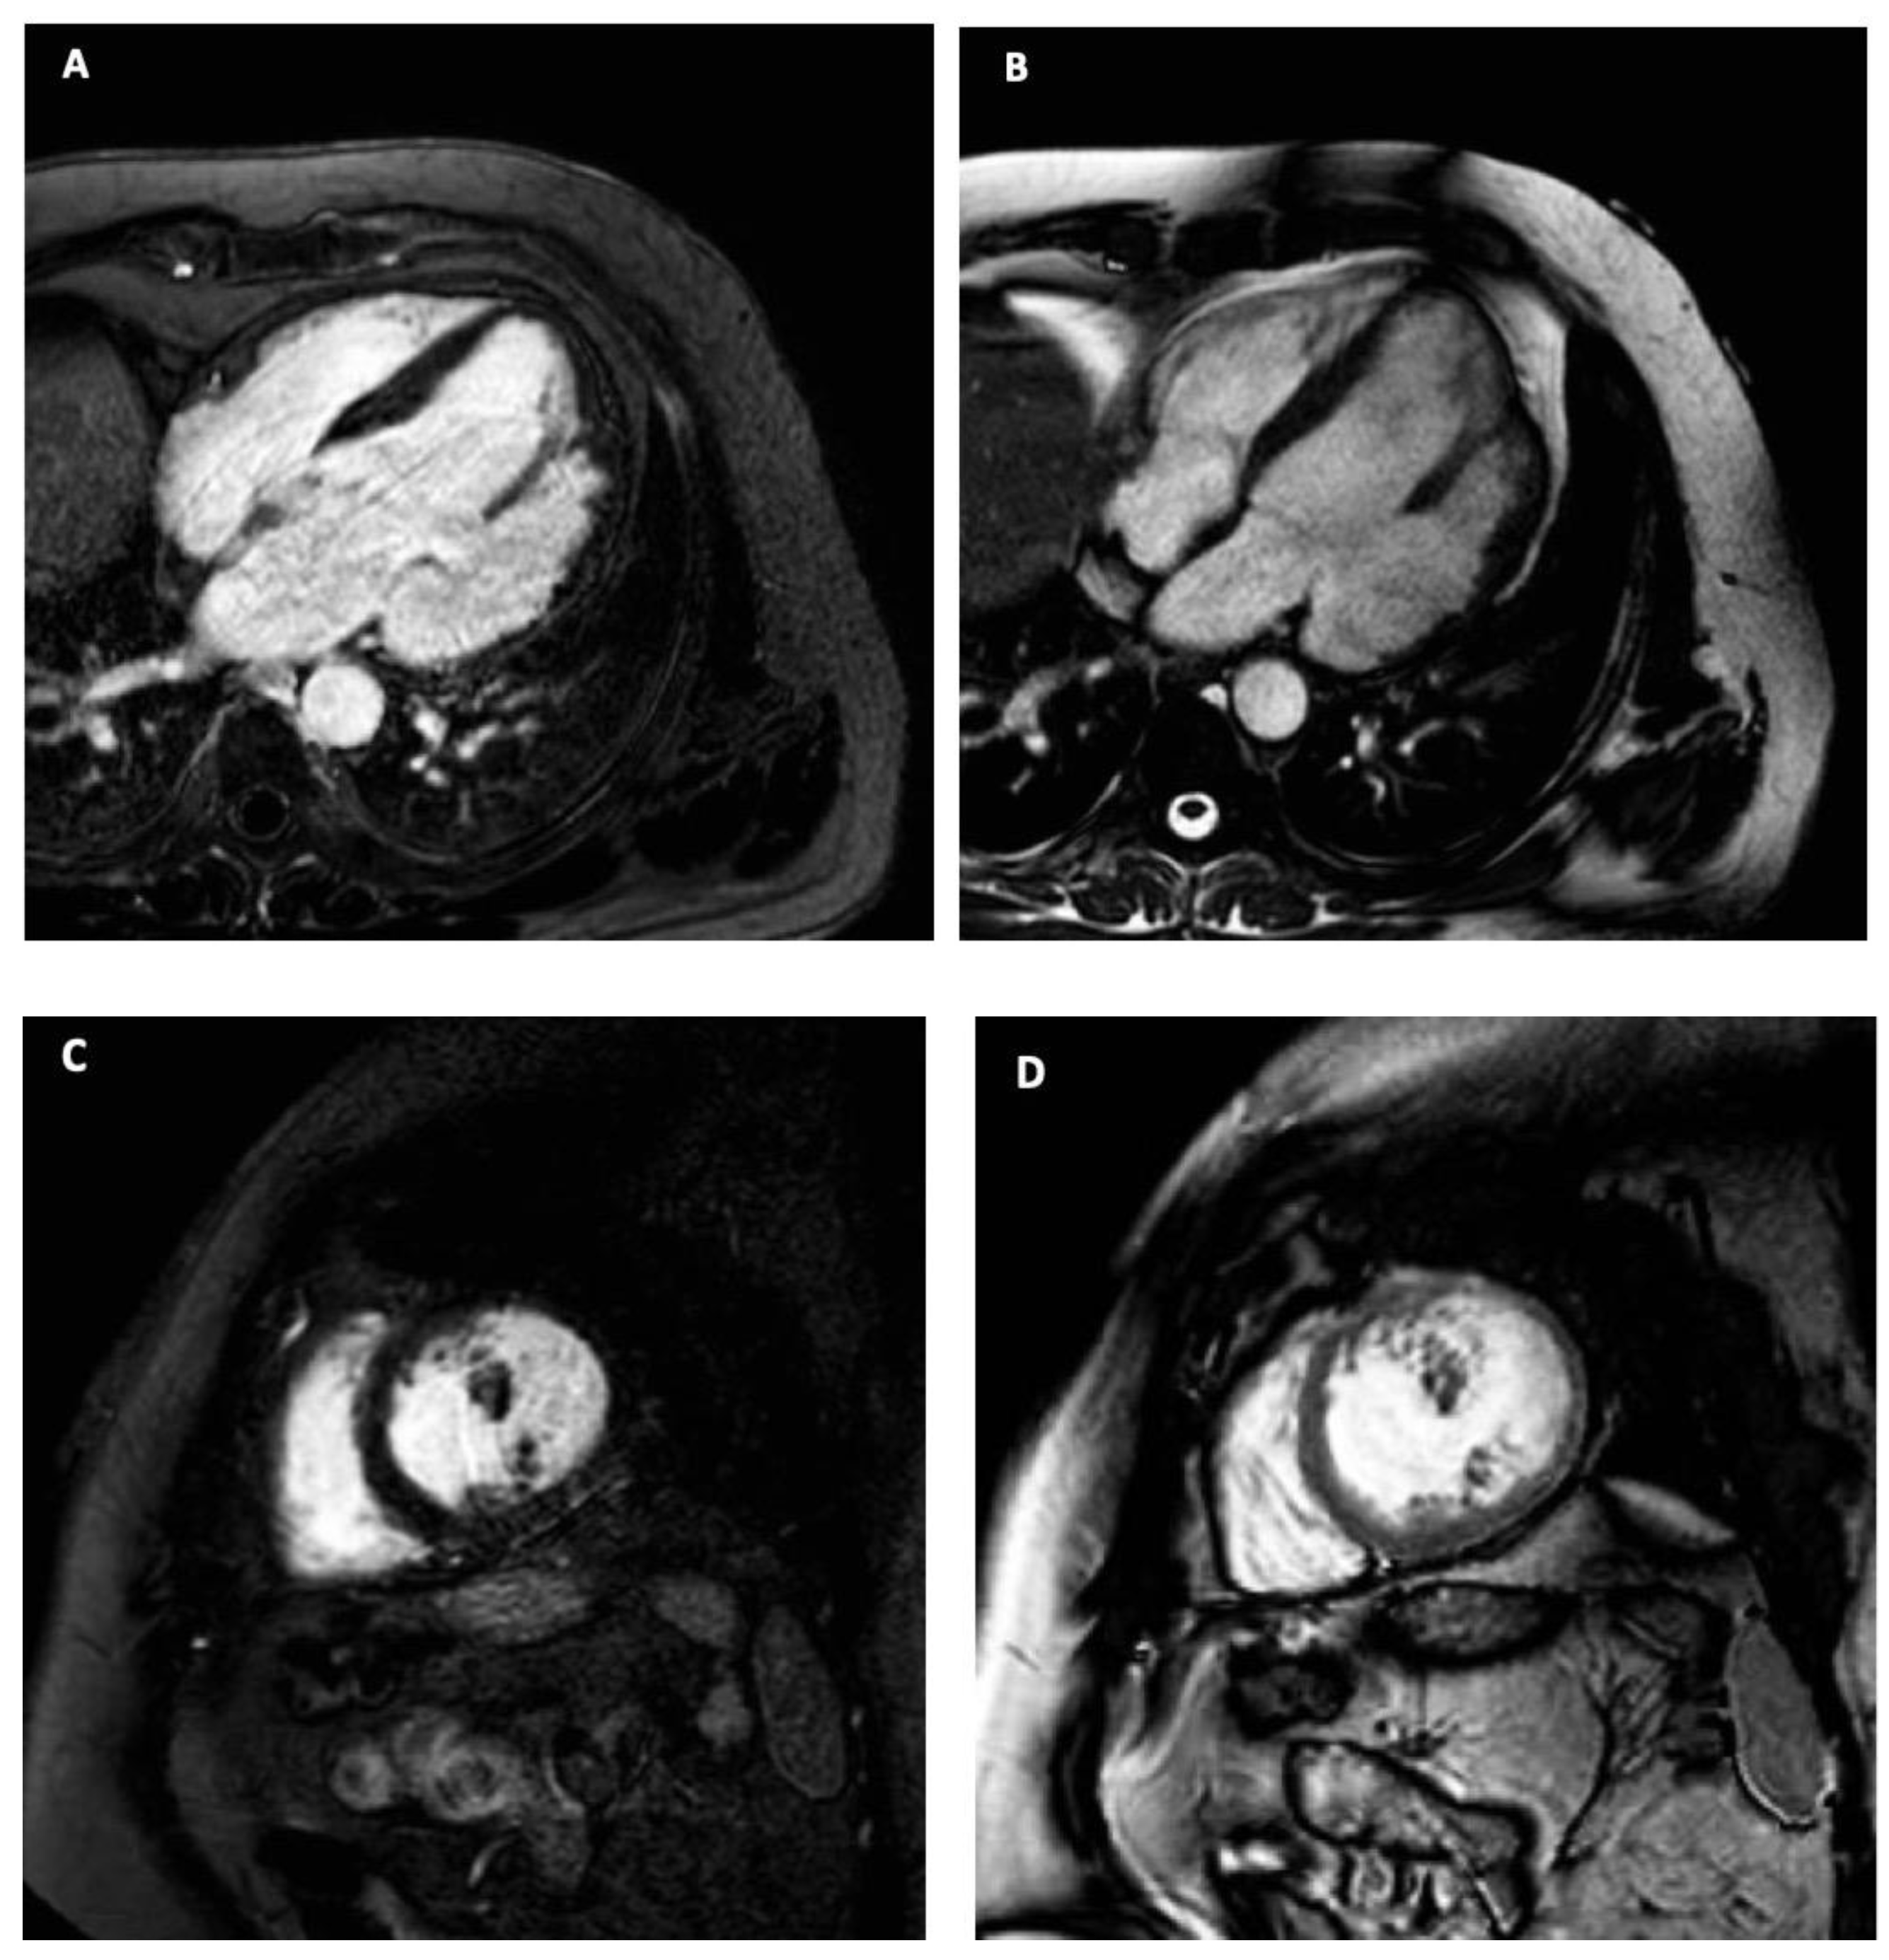

- Sharma, A.; Kumar, S. Overview of left ventricular outpouchings on cardiac magnetic resonance imaging. Cardiovasc. Diagn. Ther. 2015, 5, 464–470. [Google Scholar]

| Left Ventricle | |

|---|---|

| EDV | 221 mL |

| EDVI | 122 mL/m2 |

| ESV | 139 mL |

| ESVI | 77 mL/m2 |

| LVEF | 37% |

| SV | 82 mL |

| SVI | 42 mL/m2 |

| CO | 6.31 L/min |

| CI | 3.5 L/m2/min |

| EDLVST | 10 mm |

| EDLWT | 10 mm |

| LVM | 108 g |

| LVMI | 60 g/m2 |

| Right Ventricle | |

| EDV | 152 mL |

| EDVI | 84 mL/m2 |

| ESV | 65 mL |

| ESVI | 36 mL/m2 |

| LVEF | 57% |

| SV | 87 mL |

| SVI | 48 mL/m2 |